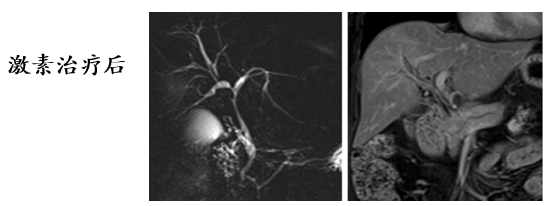

眼附属器受累

(图片均来源文末参考文献)

泪腺受累